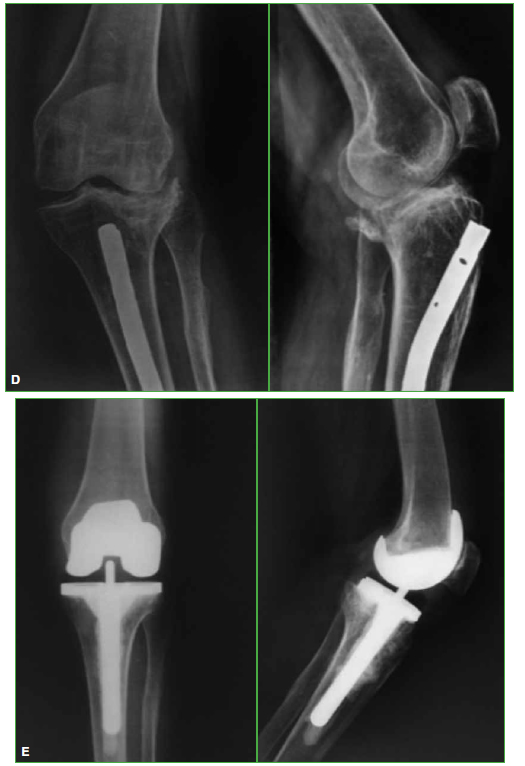

aterials and Methods: We carried out an observational, retrospective study on TKA patients treated between May 1999 and January 2013. We evaluated 25 TKAs, performed on 24 patients, with knee fracture sequela, with an average follow-up of 6.1 years and an average age of 67.1 years. Three cases (12%) had required additional surgeries before TKA. Eight cases (32%) were 2-stage surgeries. Constrained implants were used in four cases (16%). The Knee Society Score (KSS), the Functional KSS (KSSf) and the Range of Motion (ROM) were evaluated preoperatively and at the last follow-up. Prosthesis survival evaluation was documented.

Results: KSS increased from a preoperative average of 38.5 to a postoperative average of 82.8. Postoperative KSSf increased on average from 48 to 85. ROM increased on average from 7.5°-76° to 1°-102.4°. Four patients required a second surgical procedure. Prosthesis survival was 92% at a 6.1-year average follow-up.

Conclusion: TKA is an appropriate treatment for advanced PTOA, with good mid-term outcomes. If adequate postoperative alignment and correct component positioning is achieved, expected outcomes are satisfactory and similar to those with TKA in primary osteoarthritis.